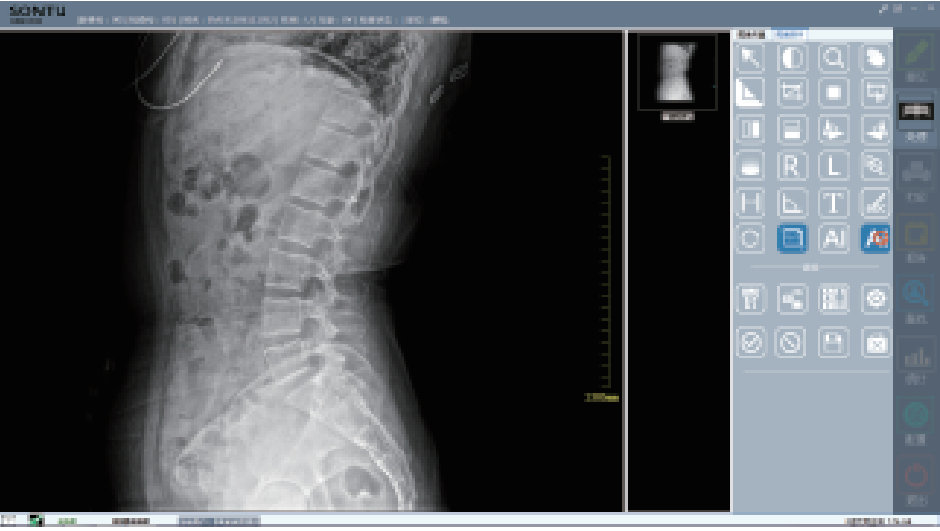

-

图像采集

-

图像操作

- 02

数字化透视:

为全身各部位透视、透视下定位、透视下穿刺及透视下数字点片摄影

- 03

数字化摄影:

为全身各部位摄影,包括常规立位、卧位摄影等(如胸片、颈椎、腰椎、腹部等)和特殊倾斜、角度摄影(如髌骨轴位、跟骨轴位等)

- 04

深图软件操作系统:

一键即可完成辅助诊断,定位可疑病变

- 05

深图AI辅助诊断系统标注示意:

标注异常位置、呈现病变信息